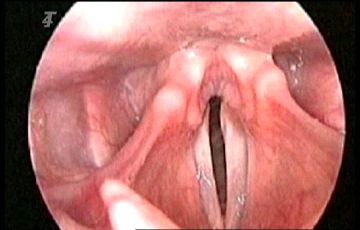

H's vocal cords.